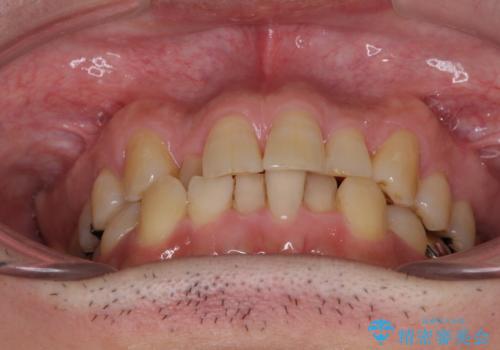

- 近医にてブリッジ治療を行った歯が痛くてたまらないとのことで来院された患者様です。

診察を行ったところ、奥の土台になっている歯は神経組織が失活しており、根尖部に病変があり、そこが原因で痛みを生じている状態でした。

根管治療を行うためにブリッジを除去したところ、むし歯が歯肉の奥深くにあまで及んでいたため、歯周外科処置によりむし歯が歯肉縁より浅い位置へと改善することとしました。

ここまでの治療を提案したところで、折角なのでしっかり治療を行いたいとのことで、前歯のデコボコやクロスバイトを改善するための矯正治療を行うこととしました。

まずは奥歯の痛みを改善し、その後矯正治療を行い、最後にオールセラミックブリッジによる補綴治療を行うこととしました。

むし歯をきっかけに矯正治療を行うこととなりましたが、学生の頃から気になっていた歯列を改善することができ、患者様には大変満足していただけました。